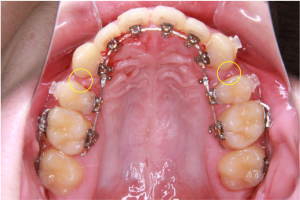

※便宜抜歯後の上顎咬合面

写真の黄色い丸で示している部分は、上あごの左右の小臼歯を抜歯したことでできたスペースです。

写真を撮影した時点では、前歯が少しずつ後ろへ移動し、奥歯も前方へ動くことで、このスペースは徐々に閉じてきている状態でした。